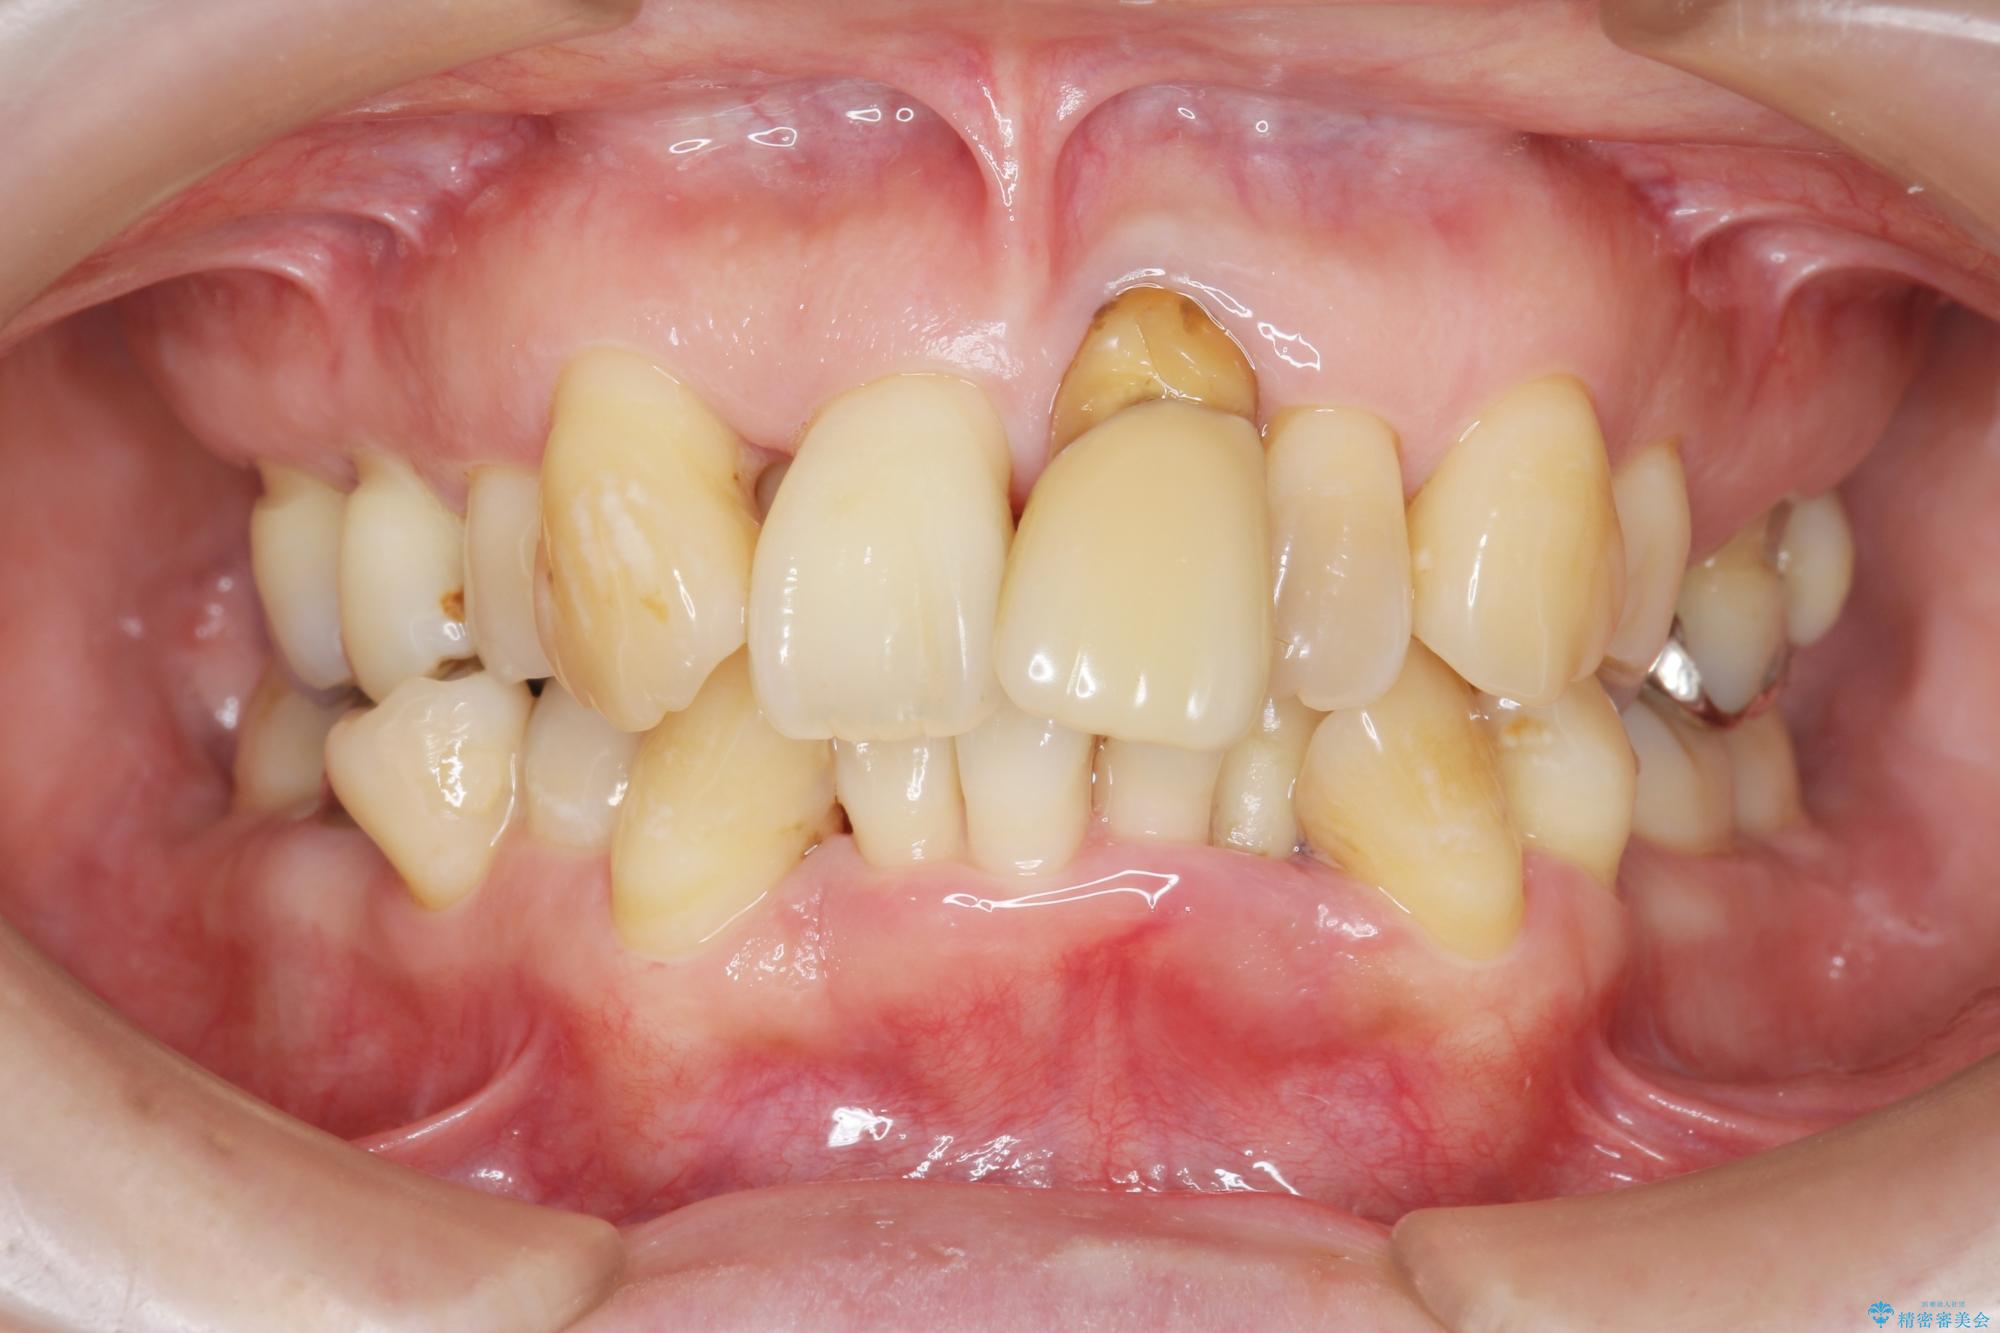

治療中

歯の総合的なマネージメントを行う包括的歯科治療の実践[ 歯周病・矯正・セラミック補綴 ] 治療中画像 歯の総合的なマネージメントを行う包括的歯科治療の実践[ 歯周病・矯正・セラミック補綴 ] 治療中画像 歯の総合的なマネージメントを行う包括的歯科治療の実践[ 歯周病・矯正・セラミック補綴 ] 治療中画像 歯の総合的なマネージメントを行う包括的歯科治療の実践[ 歯周病・矯正・セラミック補綴 ] 治療中画像 歯の総合的なマネージメントを行う包括的歯科治療の実践[ 歯周病・矯正・セラミック補綴 ] 治療中画像 歯の総合的なマネージメントを行う包括的歯科治療の実践[ 歯周病・矯正・セラミック補綴 ] 治療中画像 歯の総合的なマネージメントを行う包括的歯科治療の実践[ 歯周病・矯正・セラミック補綴 ] 治療中画像 歯の総合的なマネージメントを行う包括的歯科治療の実践[ 歯周病・矯正・セラミック補綴 ] 治療中画像 歯の総合的なマネージメントを行う包括的歯科治療の実践[ 歯周病・矯正・セラミック補綴 ] 治療中画像 歯の総合的なマネージメントを行う包括的歯科治療の実践[ 歯周病・矯正・セラミック補綴 ] 治療中画像 歯の総合的なマネージメントを行う包括的歯科治療の実践[ 歯周病・矯正・セラミック補綴 ] 治療中画像